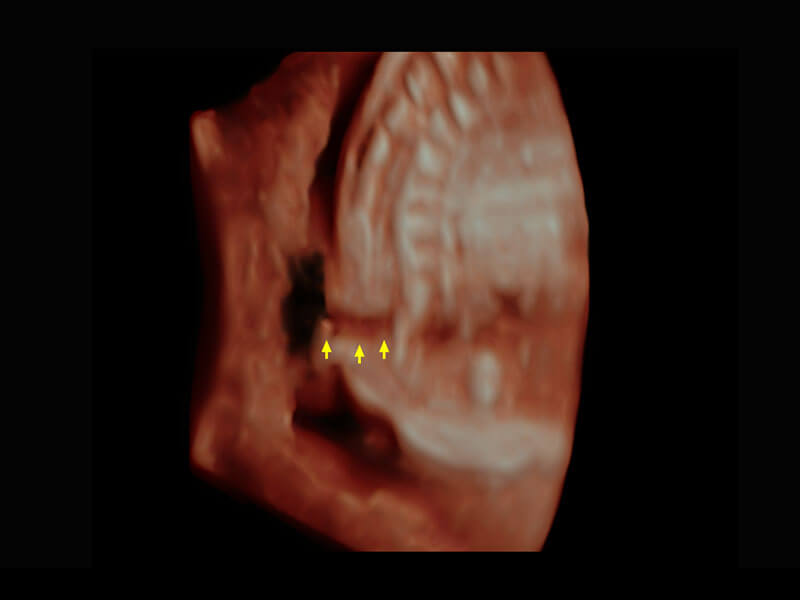

P60搭载一系列胎儿心脏成像技术,实现精细的胎儿心脏评估。

四腔切面

四腔心血流

右室双出口

胎心容积成像